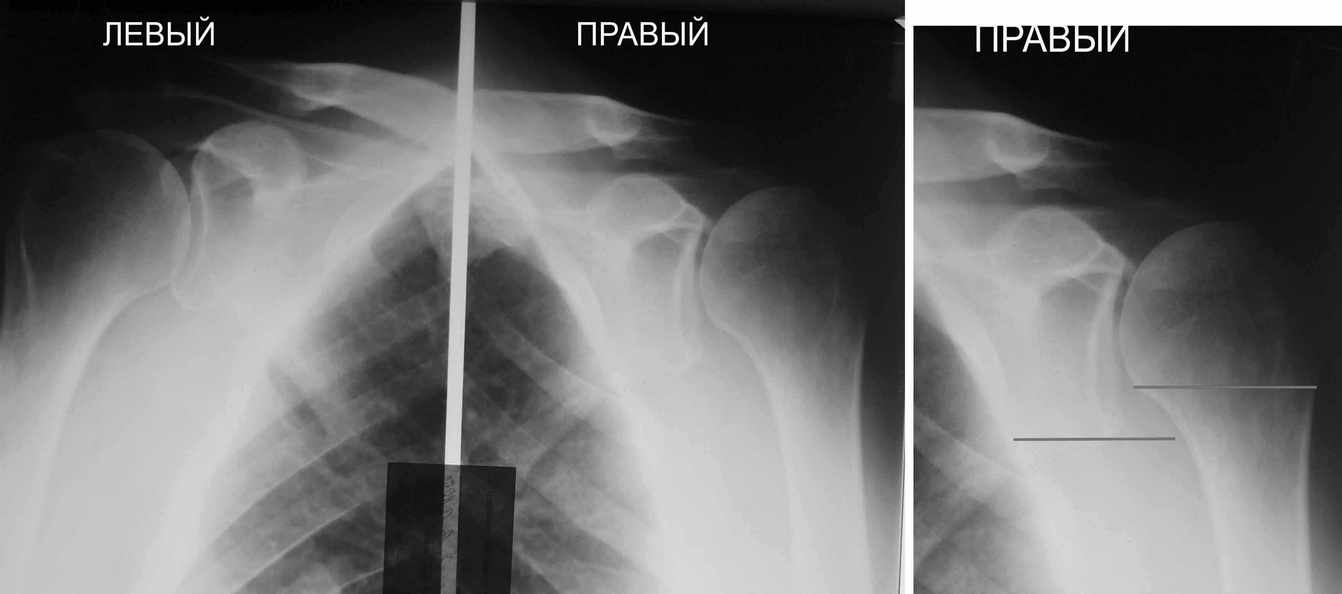

В качестве примера - снимки до и после восстановления целостности вращательной манжеты после 3-хмесячной давности полного разрыва. Видно, что верхний подвывих устранен.